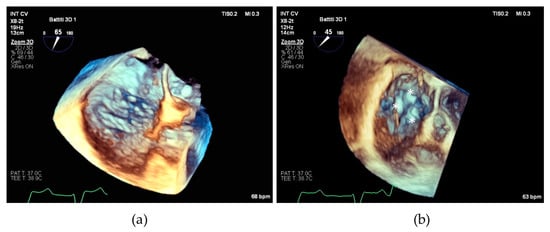

It is worth noting that both the SL-LAI and AP-LAI were significantly different in the two groups; however, the group with suboptimal results had a higher SL-LAI, an unexpected result since this condition should theoretically represent a more favorable anatomy for TEER according to the previous literature. Conversely, AP-LAI was significantly lower in the suboptimal result group (0.5 ± 0.2 vs. 0.7 ± 0.1, p < 0.05) (see Figure 3).

Figure 3. Boxplots showing differences in SL-LAI (a) and AP-LAI (b) in the two groups of patients with suboptimal and optimal results. SL-LAI—septal–lateral leaflet-to-annulus index, AP-LAI—antero-posterior leaflet-to-annulus index.